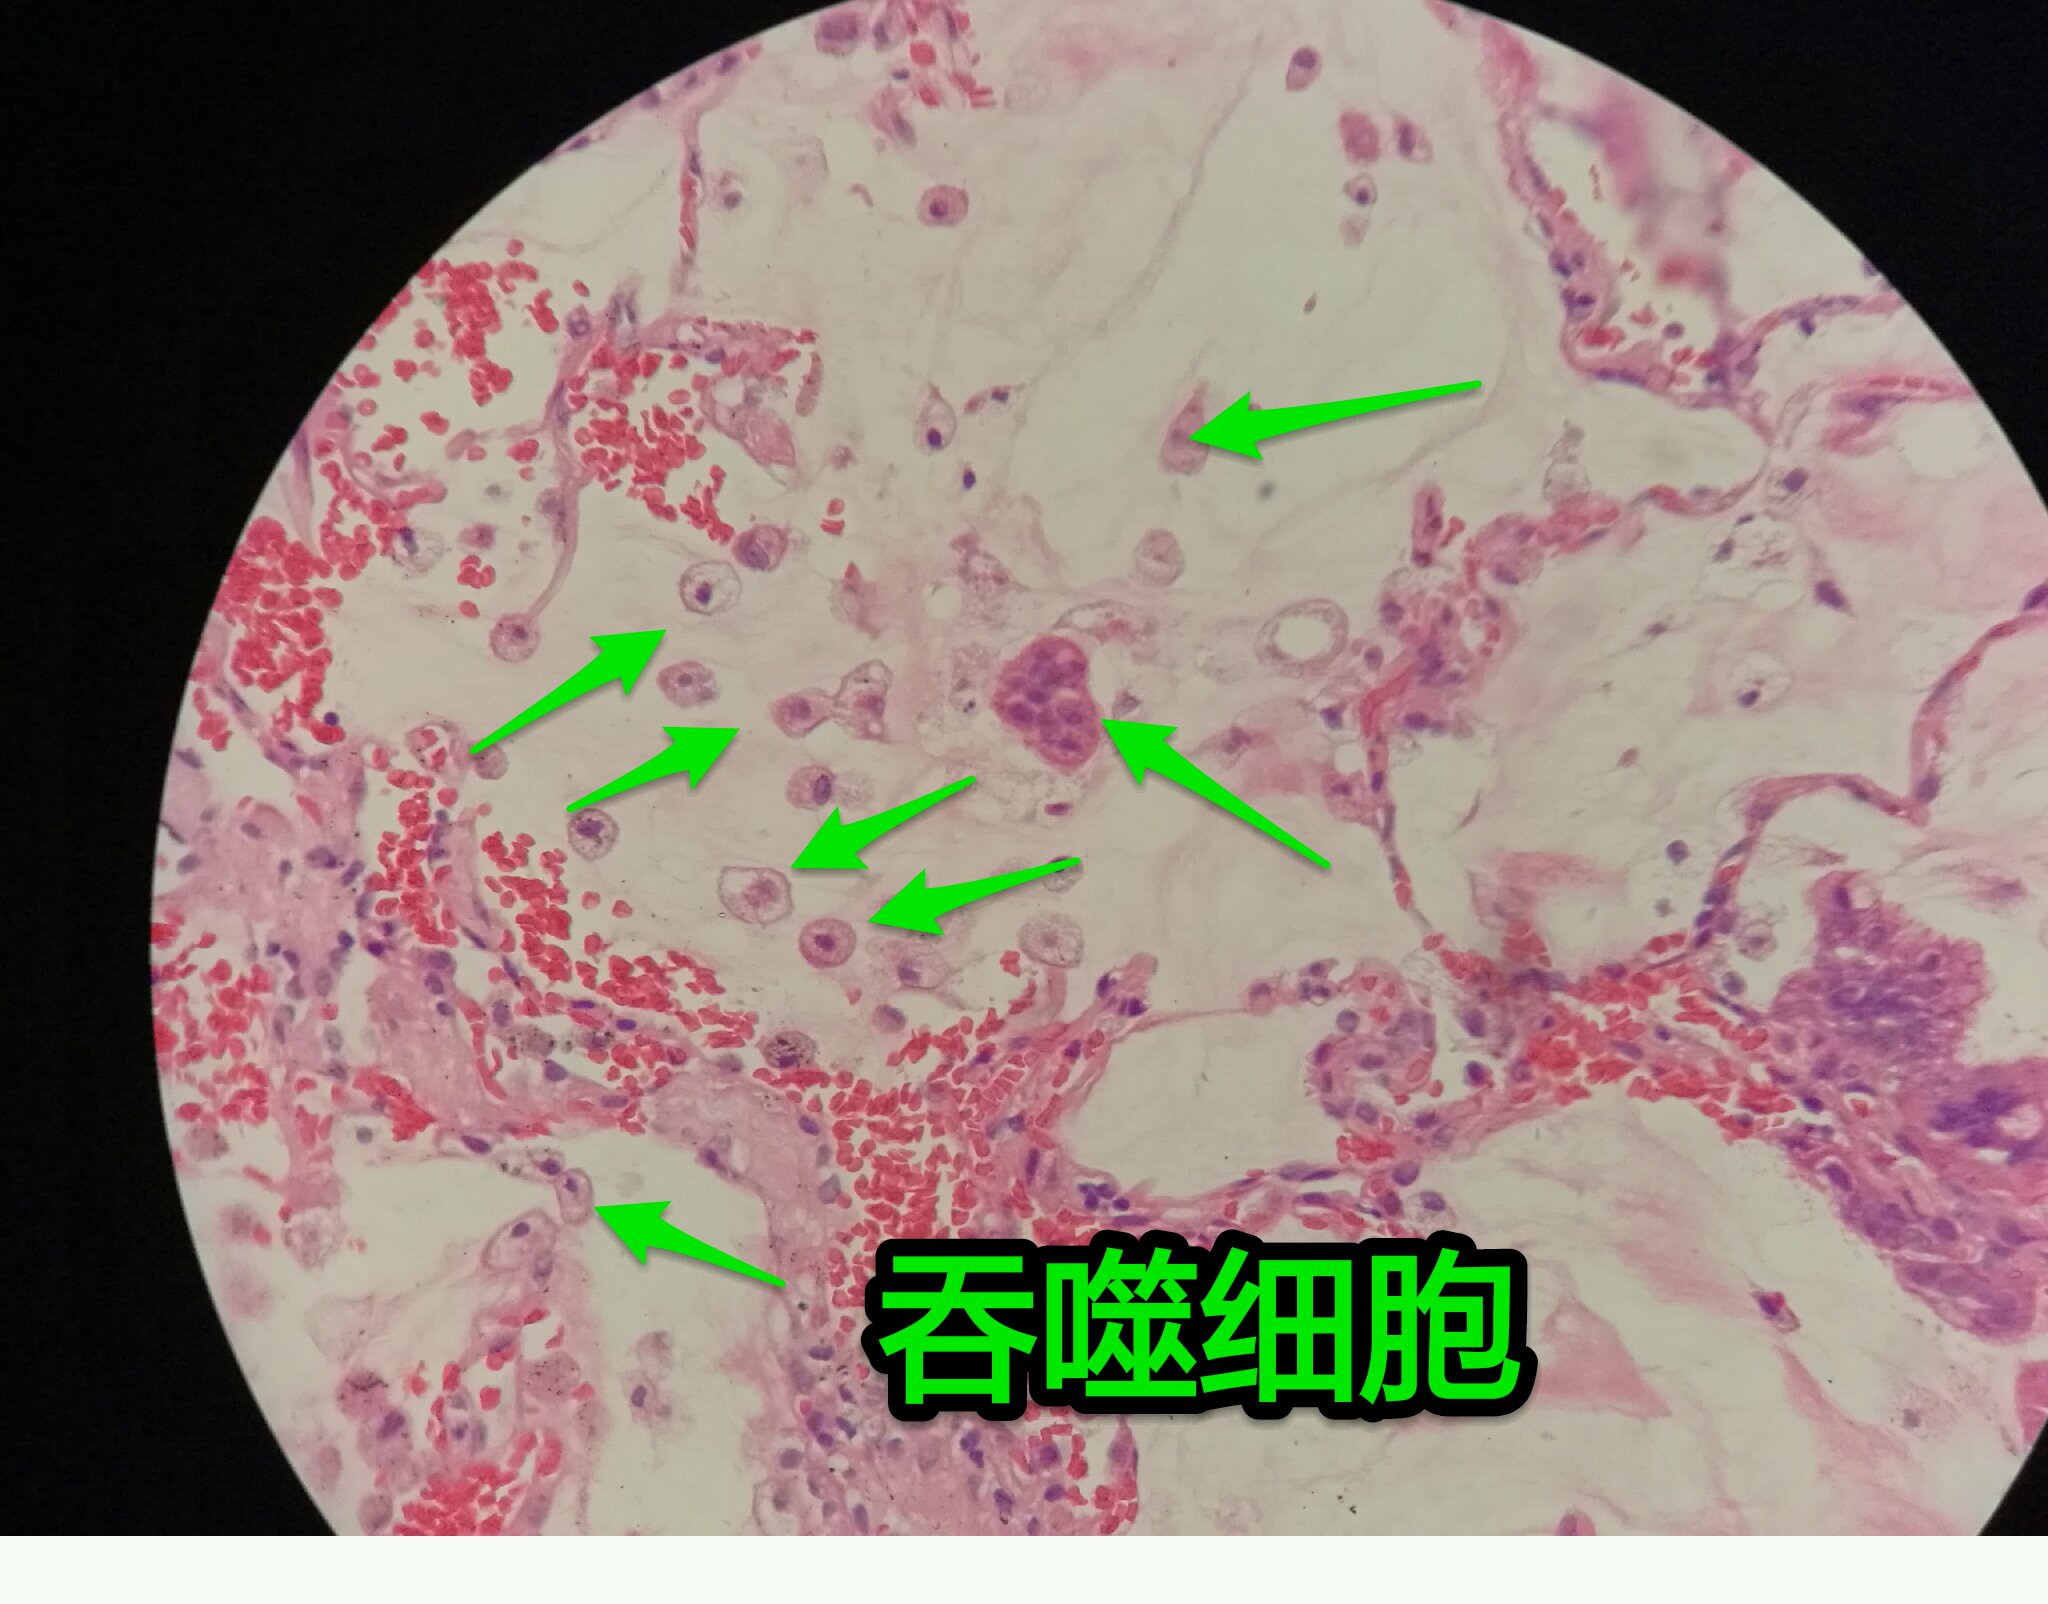

黏液湖里可以飘着一些细胞,吞噬细胞及肿瘤细胞。

肿瘤细胞飘出去可以种植于肺泡上。

肿瘤细胞堆经常是离开的

中间这一团,整个都是飘过来种植长成这样

这在进展后期特别多见

早期飘散常很近